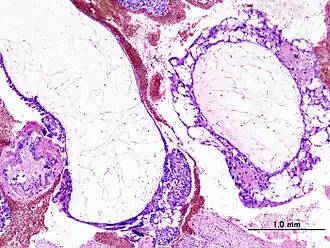

Image histologique d'une môle hydatiforme dans sa forme complète. Coloration H & E.

Un certain nombre de diagnostics de môles sont faits par l'examen anatomopathologique des résidus d'une fausse-couche[8]. Macroscopiquement, on observe dans les môles complètes une masse hémorragique constituée de multiples vésicules à paroi fine et au contenu liquidien « en grappe de raisin ». Histologiquement, c'est une prolifération de villosités hydropiques, kystiques, avasculaires. On constate surtout une hyperplasie trophoblastique diffuse[9]. Dans les môles partielle, l'hyperplasie trophoblastique est moins marquée et des villosités normales cohabitent avec des villosités hydropiques[10].